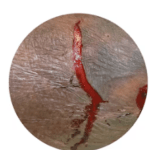

Enrolled Nurse (EN): Permitted Procedures

This page provides a quick reference of Care Plans and Tutorials available on The Wound Sandwich (TWS) which are permitted to be undertaken by staff with a Enrolled Nurse (EN) qualification. Additional applicable qualifications are also listed.